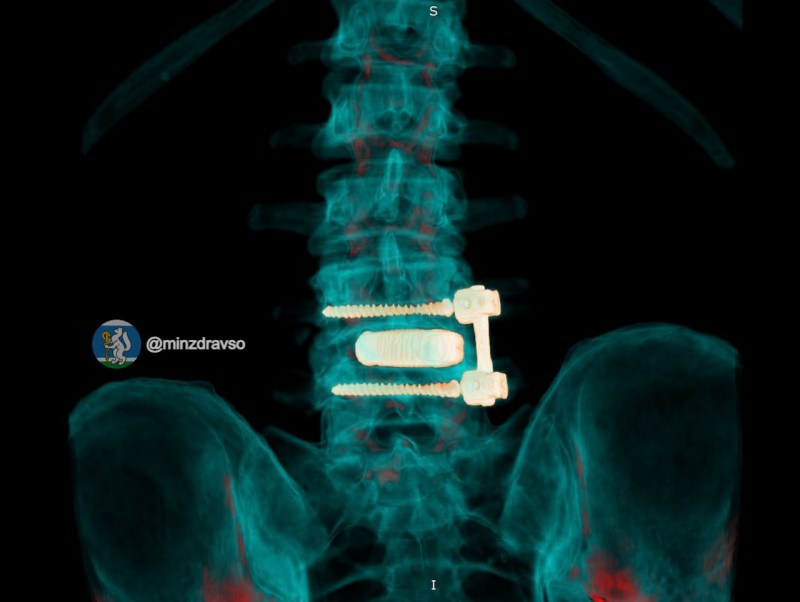

Нейрохирурги Свердловского госпиталя для ветеранов войн спасли 52-летнего водителя скорой помощи, у которого после давней операции на поясничном отделе позвоночника развилась инфекция.

Как рассказали в официальном телеграм-канале областного министерства здравоохранения «Здоровье уральцев», организм стал отторгать ранее установленную конструкцию, и у мужчины развилась периимплантная инфекция. Состояние резко ухудшалось: в какой-то момент водитель скорой упал из-за внезапной слабости и сломал лодыжку.

Лечить мужчину стали в госпитале для ветеранов войн, где ему сначала удалили инфицированную конструкцию и провели санацию очага воспаления, а затем после курса антибактериальной терапии восстановили опороспособность позвоночника с помощью титанового 3D-импланта, изготовленного по индивидуальным параметрам.

«Фиксацию выполнили российскими спонгиозными винтами. Уже в первые сутки после операции болевой синдром полностью купировался, пациент самостоятельно встал и начал ходить»,